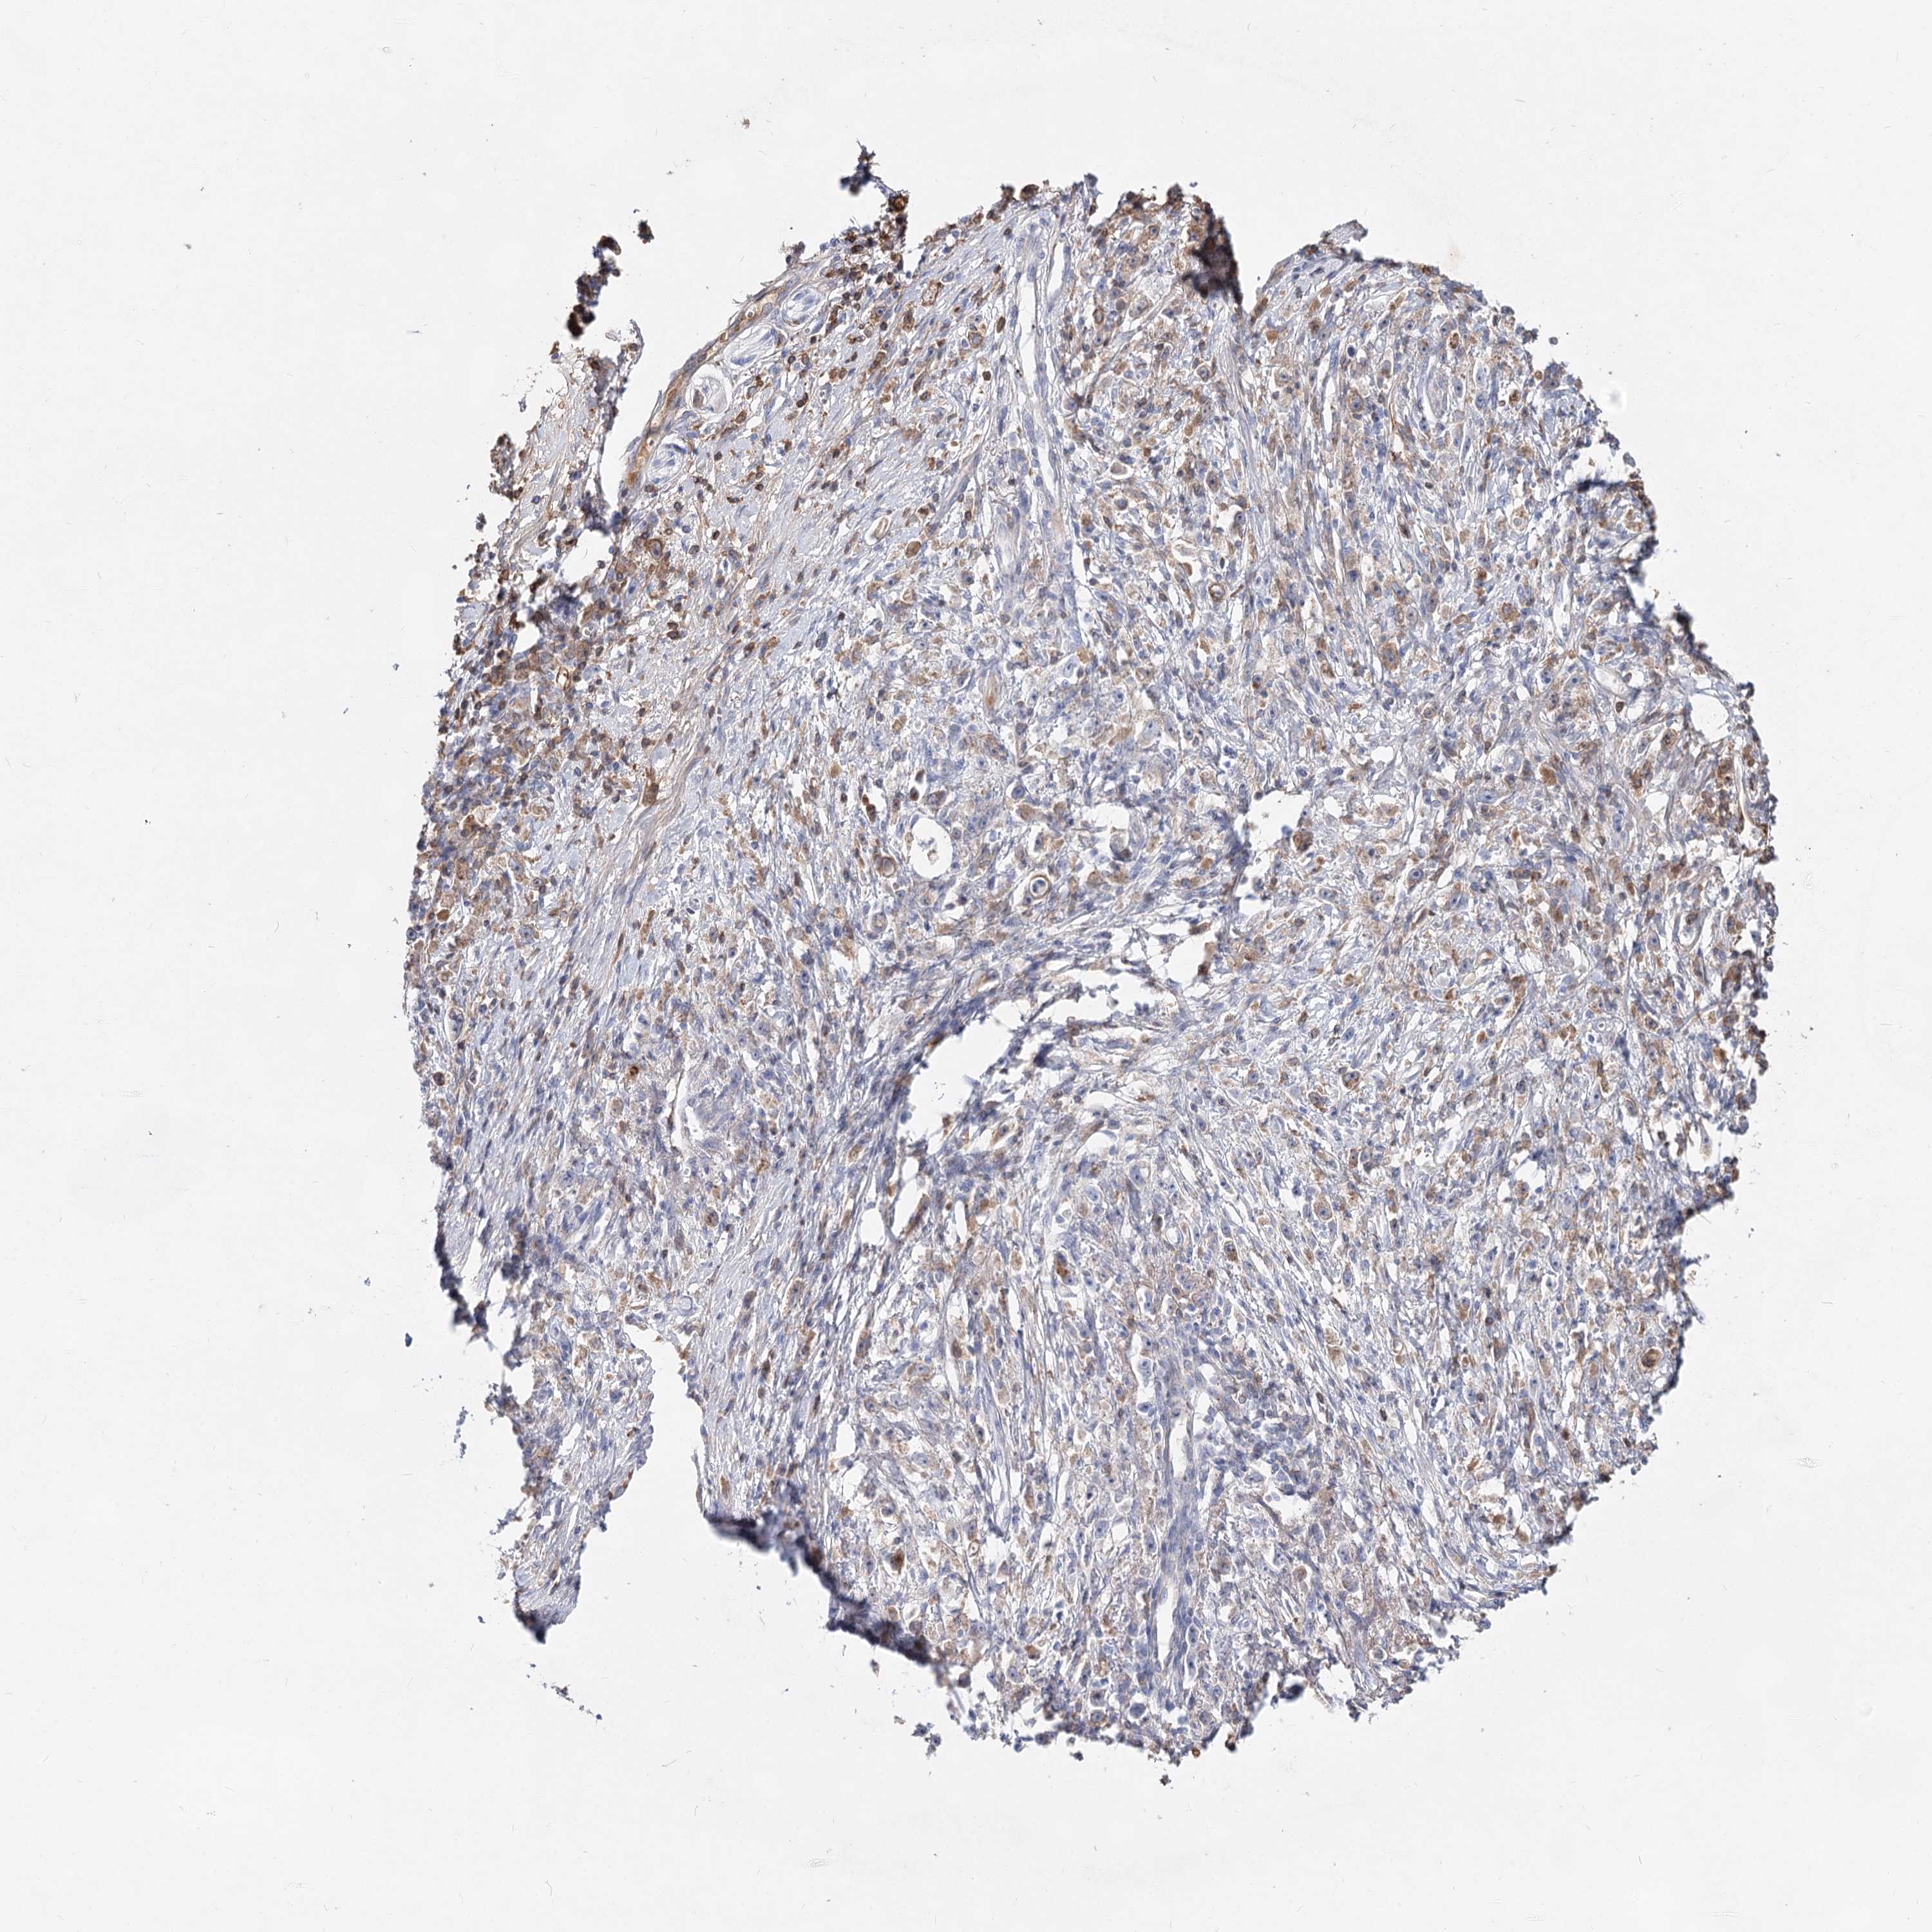

STOMACH CANCER - Protein expressioni

A mouse-over function shows sample information and annotation data. Click on an image to view it in a full screen mode. Samples can be filtered based on level of antibody staining by selecting one or several of the following categories: high, medium, low and not detected. The assay and annotation is described here.

Antibody stainingi

Antibody staining in the annotated cell types in the current human tissue is reported as not detected, low, medium, or high, based on conventional immunohistochemistry profiling in selected tissues. This score is based on the combination of the staining intensity and fraction of stained cells.

Each image is clickable and will lead to virtual microscopy that enables deeper exploration of all samples and also displays staining intensity scores, fraction scores and subcellular localization as well as patient and tissue information for each sample.

Antibody HPA038042

Antibody HPA038043

Staining

High

Medium

Low

Not detected

Intensity

Strong

Moderate

Weak

Negative

Quantity

>75%

75%-25%

<25%

None

Location

Nuclear

Cytoplasmic/membranous

Cytoplasmic/membranous,nuclear

Adenocarcinoma, NOS

Adenocarcinoma, High grade